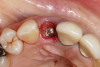

Fig 5. Atraumatic extraction without raising the flap, with the intention of minimizing bone loss, especially in the interproximal area.

Figure 5

To predict peri-implant esthetic outcomes, Kois described five essential diagnostic keys that need to be assessed before removing a periodontally hopeless tooth (Figure 3 and Figure 4): (1) relative tooth position; (2) form of the periodontium; (3) periodontal biotype; (4) tooth shape; and (5) position of the osseous crest. Failing teeth that have a thick, flat gingival biotype, are square shaped, and have < 3 mm vertical distance from the position of the facial and interproximal crest have the lowest risk of developing recessions after implant placement.23 Therefore, implant surgery may be performed by either an open flap or flapless approach. However, teeth with a thin soft-tissue biotype, a highly scalloped gingival architecture, and a triangular shape that are positioned facially have less-predictable peri-implant esthetic outcomes. When a tooth presents with these unfavorable anatomical features, grafting procedures should be considered both before and after tooth extraction to prevent vertical loss and facial collapse of the gingival architecture.21 Flapless tooth extraction should be attempted in the esthetic zone to maintain blood supply from the periosteum and endosteum and maximize healing potential (Figure 5).44 In addition, several surgical protocols have been proposed to avoid peri-implant mucosal recessions, including 3-dimensional implant positioning,45,46 the use of platform-switching implants,47,48 and soft-tissue augmentation.8,49,50